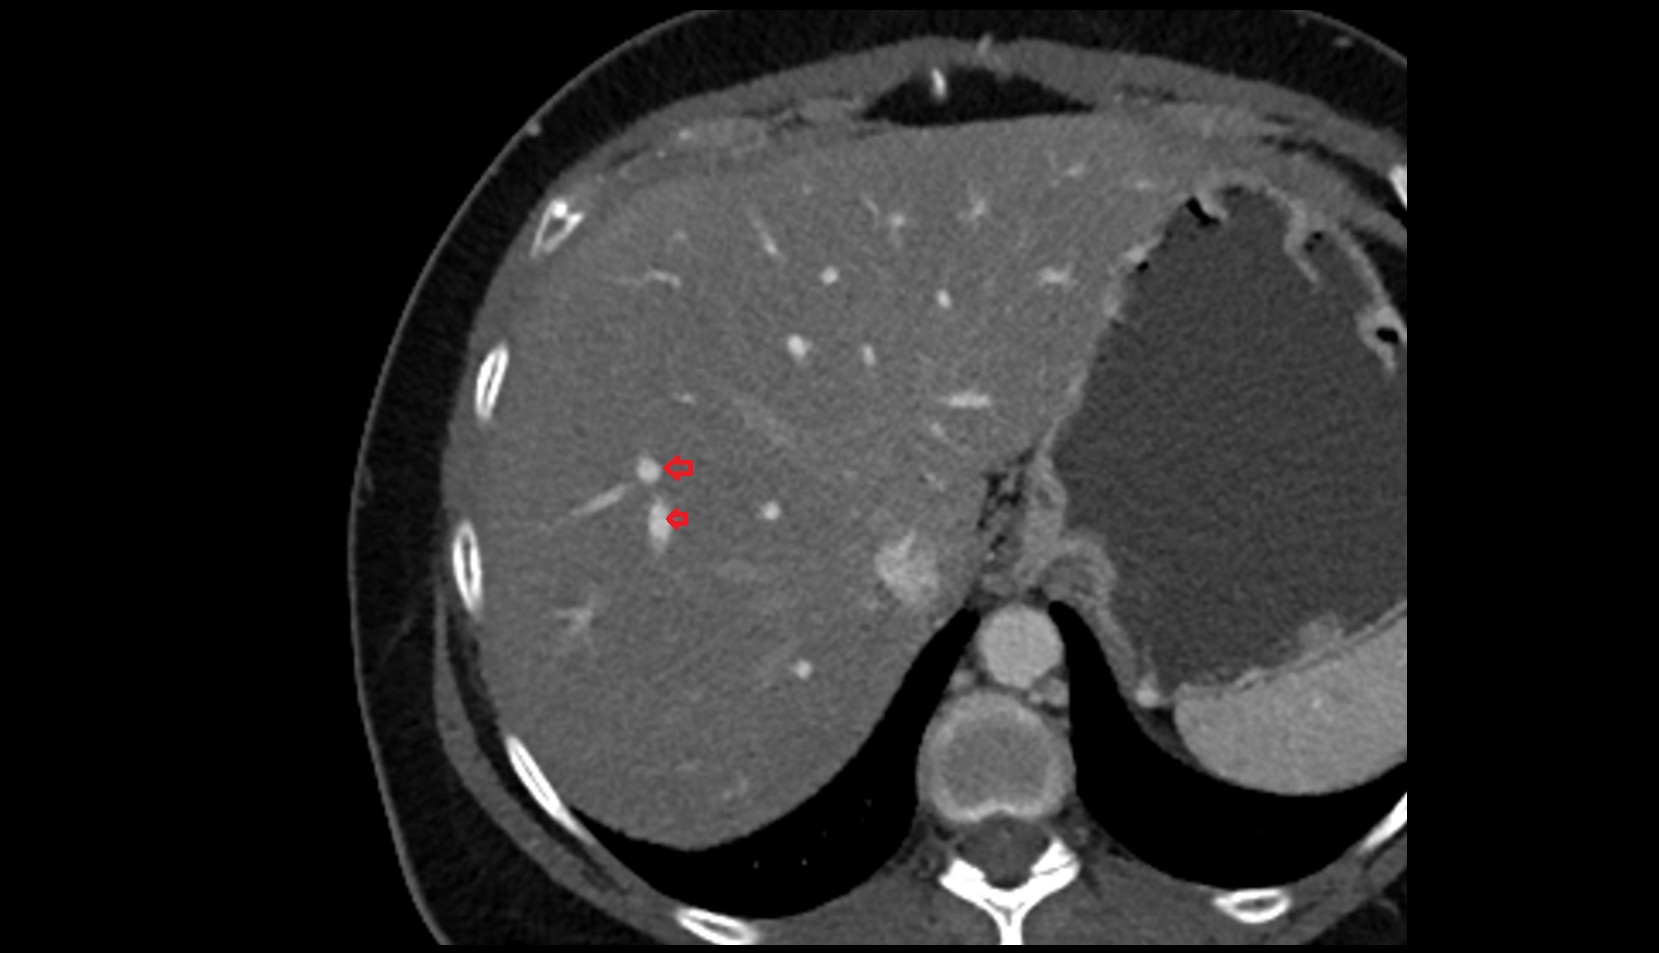

- Right lobe of liver

- Liver

- Liver Segment I – Caudate lobe

- Liver Segment II – Left lateral superior segment

- Liver Segment III – Left lateral inferior segment

- Liver Segment IVa – Left medial superior segment

- Liver Segment IVb – Left medial inferior segment

- Liver Segment V – Right anteroinferior segment

- Liver Segment VI – Right posteroinferior segment

- Liver Segment VII – Right posterosuperior segment

- Liver Segment VIII – Right anterosuperior segment